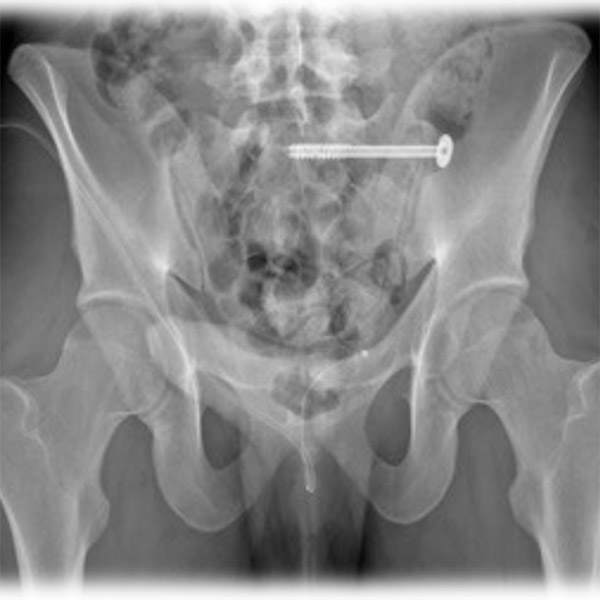

Verletzungen des hinteren Beckenrings erfordern häufig eine Verschraubung des Iliosakralgelenks (ISGs) (siehe Abbildung 1). Nach einem solchen Eingriff kann es zu Einschränkungen des Gangbildes der Patienten kommen. Das nachfolgend beschriebene Projekt stellt eine Methode vor, mit der Unterschiede im Gangbild von Patienten nach einer perkutanen Iliosakralgelenksverschraubung (ISG-Verschraubung) des hinteren Beckenrings im Vergleich zu gesunden Studienteilnehmern objektiv untersucht werden können.